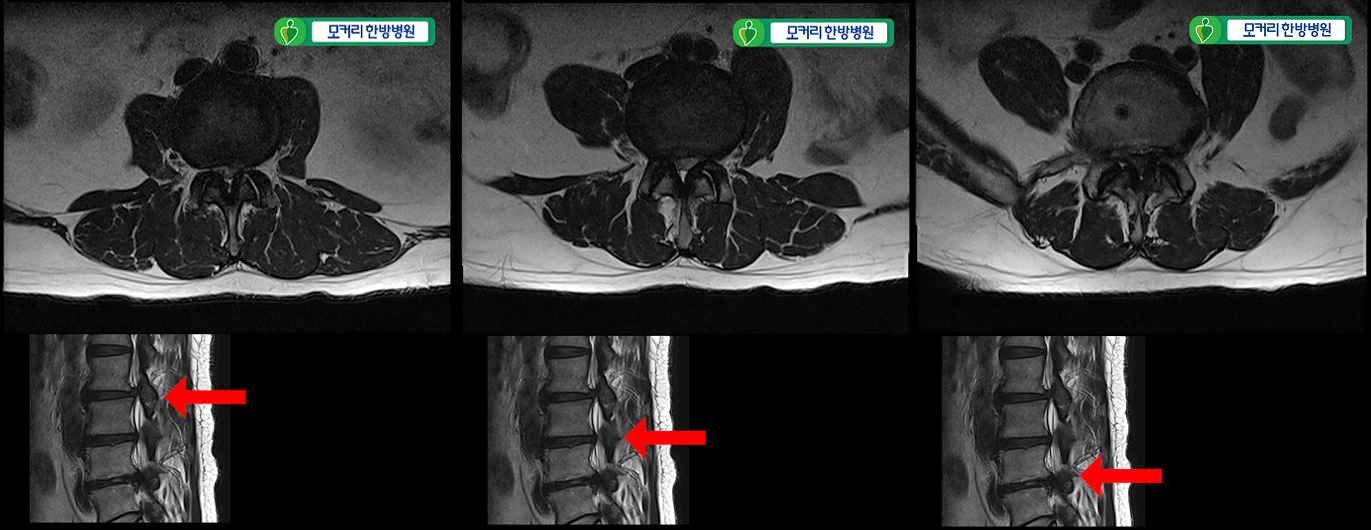

이 첫 번째 환자분은 허리 세 마디에 심한 협착이 있는 환자분으로, 2-3번, 3-4번, 4-5번 이렇게 척추관이 세 마디가 심하게 막혀있었습니다. 증상이 너무 심해 25년간 신경주사 치료를 받았지만 점차 효과가 떨어지더니 나중에는 전혀 듣지 않았습니다. 여러 마디가 안 좋다 보니까 대학병원에서는 수술이 어려우니 참고 살라고 하고, 유명 척추병원에서는 3주에 걸쳐 3번의 수술을 권했던 상태였습니다.

25년간 허리에 신경주사를 맞아왔는데 이젠 효과가 전혀 없고, 작년부터 거의 걷지 못하는 상태가 되어 수술을 결심하였습니다. 대학병원에서 수술이 어렵다고 했고 유명 척추병원에서 3주에 걸쳐 3번의 수술을 권했습니다.